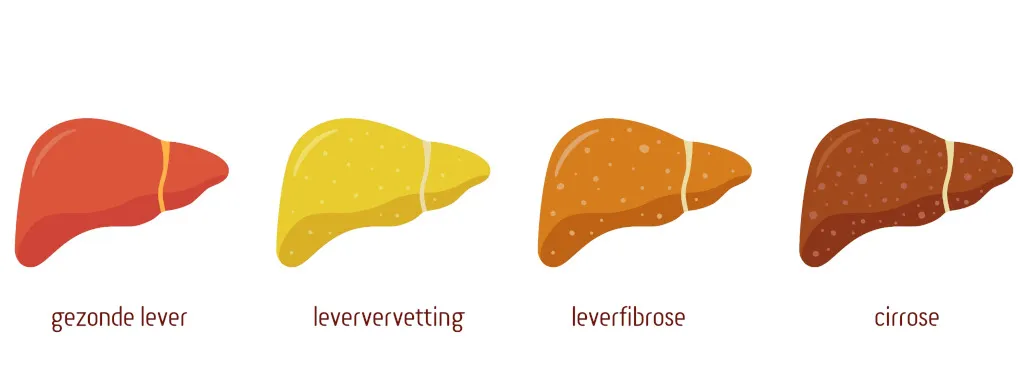

Studies met muizen tonen aan dat ijzertekort en mitochondriaal ijzertransport (via mitoferrine-2, een ijzertransporter in de darm) het levervetmetabolisme en leververvetting beïnvloeden. De darmmicrobiota blijkt cruciaal te zijn in de ijzerhuishouding en leverstofwisseling. Beperking van ijzer in de voeding beïnvloedde de samenstelling van de darmmicrobiota, ijzerabsorptie en ijzerniveaus in weefsels bij de dieren. Minder ijzer in de voeding leidde tot vetophoping in de lever door metabole disfunctie en metabool syndroom bij de muizen. Germ-free (GF) muizen, die geen microbiota hebben, waren beschermd tegen deze effecten.

Een laag ijzergehalte in de voeding leidde tevens tot een verhoogde concentratie triglyceriden in het bloed van de dieren. GF-muizen op een ijzerarm dieet vertonen minder ophoping van deze toxische vetten, wat suggereert dat bepaalde microben de leverstofwisseling negatief kunnen beïnvloeden.

Deze bevindingen benadrukken dat ijzertekort, een veelvoorkomend voedingsprobleem, leververvetting door metabole disfunctie kan veroorzaken en dat het aanpassen van de darmmicrobiota bescherming kan bieden. Vervolgonderzoek moet de klinische effectiviteit van therapie met bijvoorbeeld probiotica beter in kaart brengen.